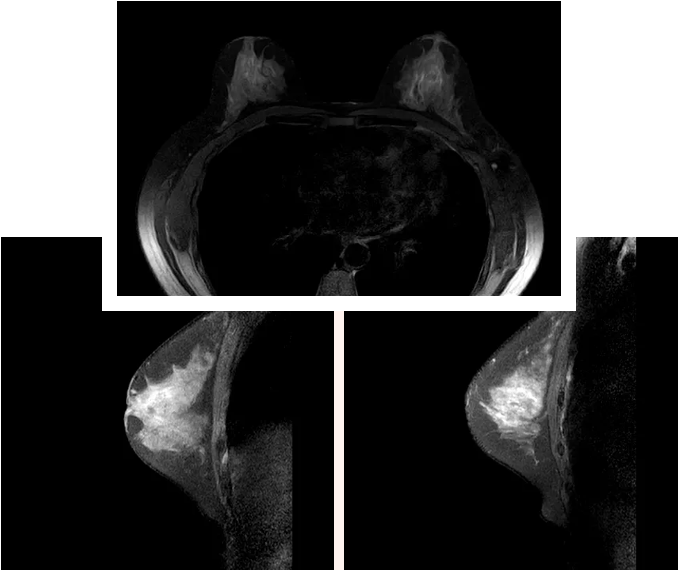

乳腺磁共振(MRI)借助强磁场与无线电波的神奇力量,能为乳腺拍摄百万像素级的 “高清写真”,那些连超声和钼靶都可能遗漏的微小细节,它都能精准捕捉!它的三大 “超能力”,堪称乳腺健康的 “安全卫士”:

许多亚洲女性存在腺体致密的情况,这会让普通检查如同隔着毛玻璃,难以看清内部状况。而乳腺磁共振就像拥有 “透视眼”,能够轻松穿透致密组织,清晰呈现隐藏的病灶!

它的侦查能力堪称一绝,哪怕是< 5 毫米的恶性病灶也无处遁形,敏感性高达 90% 以上!在癌症还处于萌芽阶段时,就能及时拉响警报,为治疗争取宝贵时间。